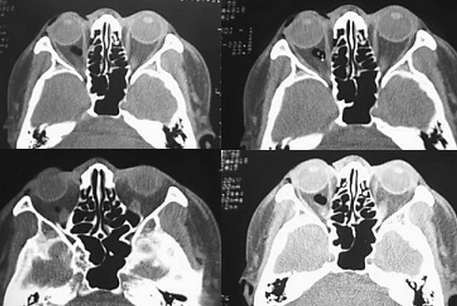

男45y3小时前被打伤眼部,无鼻出血,hrct示右眼眶内壁眼内直肌内侧有积气,可不可以定为眶内壁骨折???

层面上传不够,考虑眶内壁骨折。

若hrct示右眼眶内壁眼内直肌内侧是积气,应该可以认为是眶内壁骨折的间接征象,筛骨纸板很薄,容易发生骨折。

可以考虑眶内壁骨折,能不能缩小显视野,将图像放大观察,第一幅图像气体影处有一小致密结节,请上传邻近层面的图像。

本例无明显筛板中断,眶内侧气体影也不确切,眶内侧及窦腔内无渗液,内直肌不厚,虽有鼻部软组织肿胀,但还是没有太多依据诊断为筛板骨折。

2.本片支持右侧筛窦纸板骨折;

右眼眶内壁与眼内直肌间可见积气,应该可以认为是眶内壁骨折的间接征象,筛骨纸板很薄,容易发生骨折,典型的骨折较难看到。

眶内壁有缺埙,内直肌外气体影,眶内壁骨折。

以下是引用wangqj1976在2006-1-20 20:36:00的发言:[br]可以诊断右眶内侧壁骨折[br]依据:[br]1直接征象:右眶内壁骨质局限性中断,内陷.[br]2间接征象:球后间隙积气,右眶部软组织肿胀.[br]